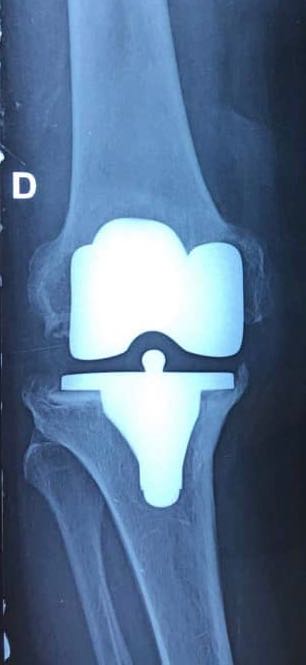

Cliquer sur une photo pour défiler la collectionPTG postero-stabilisee cimentée descellée

PTG postero-stabilisee cimentée descellée

Radio de contrôle de la PTG descellee